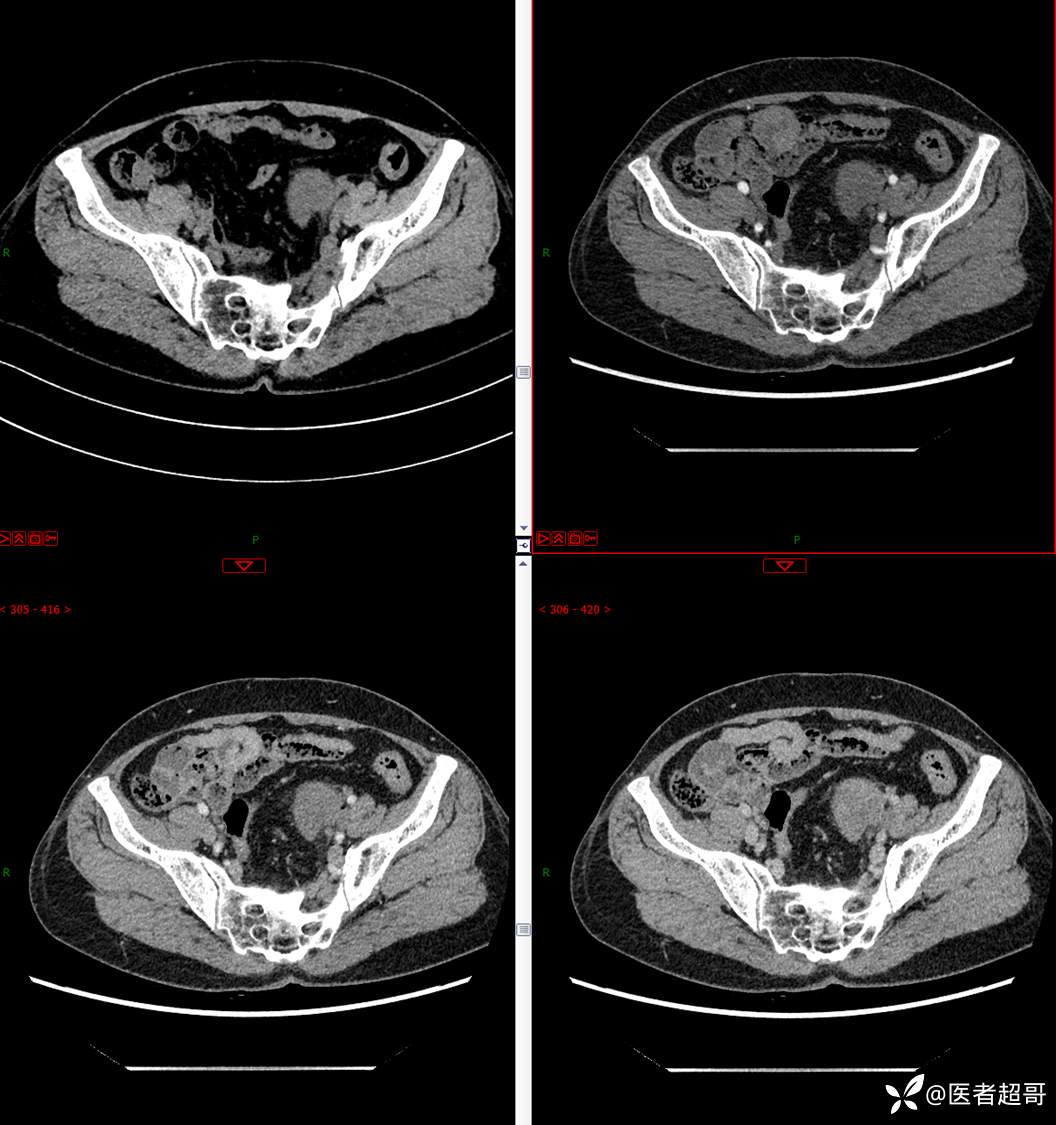

【影诊笔记559】查体发现右输尿管结石1周,发现腹膜后肿物,请分析,有病理!

•主 诉:查体发现右输尿管结石1周。

•现病史:患者1周前因小便不适来我院门诊行彩超检查提示右输尿管结石并右肾积水,伴腰疼,无血尿,无寒战,高热,患者求其进一步诊治,门诊以“右输尿管结石并右肾积水”收入院,患者自发病以来,神志清,精神可,饮食睡眠可,大便便秘,近期体重无明显增减。